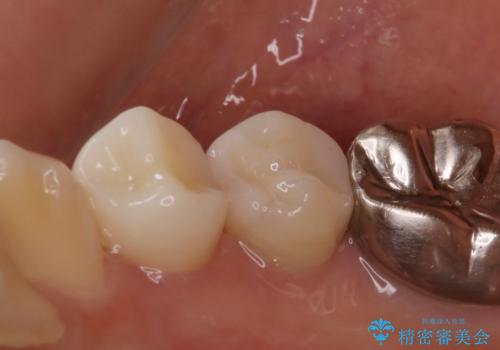

- 右下が痛くて噛めないとの理由で来院された患者様です。レントゲン撮影、歯髄の診断等から、根管治療、歯髄保存療法が必要と判断し、治療後に丈夫で審美性に優れたセラミックインレー、フルジルコニアクラウンを被せました。

治療後は痛みもなくなり、経過も良好でキレイな被せ物にも満足いただけました。